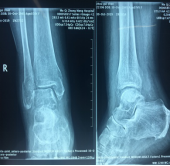

手法整复桡骨远端骨折、踝关节骨折、尺骨骨折、掌骨骨折、指骨骨折、跖骨骨折及肩关节脱位、桡骨小头半脱位等各类骨折脱位十余例,行小夹板固定及石膏托外固定十余例。